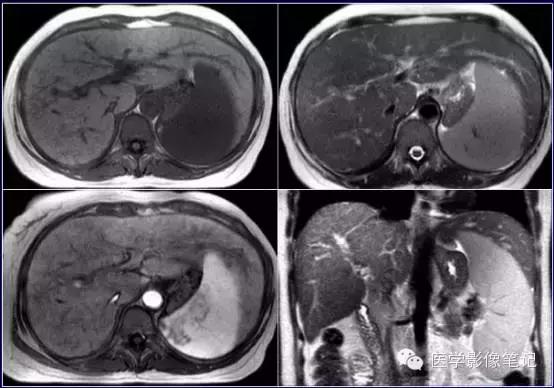

肝脏变异

獭尾肝/包围肝,见于5%的成人。

獭尾肝/包围肝

利德尔叶(Riedel’s Lobe)

肝的右下部向下如舌状突出生长的舌叶。

乳头状突

肝尾状叶结构,常误认为肿大淋巴结。

肝左叶缺如

右叶发育不全

内脏反转

咳纹肝

女性多见,由慢性咳嗽膈肌紧勒肝脏所致,也可见于过度束腰的妇女。

镰旁肝假病灶

多位于左叶内侧段或(和)左叶外侧段前缘镰状韧带旁。

机制:1、镰旁肝局部特殊血供因素;2、镰旁肝局部脂肪浸润。

来源:医学影像笔记